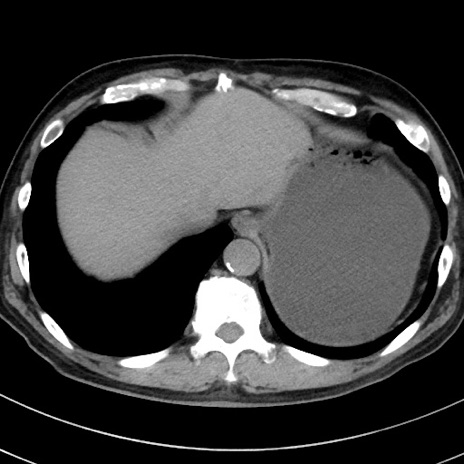

症例38(横断像)

【症例】70歳代 男性

【主訴】腹痛・嘔吐

【現病歴】昨晩より、嘔吐・腹痛あり。今朝になっても嘔吐あり。来院。

【既往歴】心臓バイパス手術、開腹胆摘、腸閉塞

【身体所見】BP 107/71mmHg、HR 116/min、腹部:平坦、軟、下腹部に軽度圧痛あり。反跳痛なし。

【データ】WBC 15100、CRP 0.32